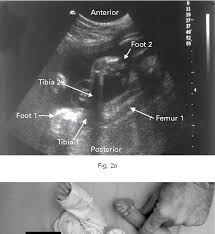

Imaging technique and findings ultrasound. Five cases of congenital clubfoot diagnosed prenatally by ultrasound are reported. Congenital talipes equinovarus is considered the most common anomaly affecting the feet diagnosed on antenatal ultrasound. The addition of microarray studies may increase the yield of invasive prenatal testing, although the complex inheritance patterns of clubfoot suggest that it rarely occurs due to a single gene mutation. 44% of fetuses underwent invasive diagnostic testing. Approximately 10% of all clubfeet can be diagnosed by 13 weeks gestation, and about 80% can be diagnosed by 24 weeks gestation. Although clubfoot is diagnosed at birth, many cases are first detected during a prenatal ultrasound. Ility of the ponseti method in correcting clubfeet; Once the child is born, the condition is clearly visible. Clubfoot can also be diagnosed by a doctor immediately after a baby is born. About 10 percent of clubfeet can be diagnosed as early as 13 weeks into pregnancy. Clubfoot may also result from a restricted environment in utero, such as from prolonged oligohydramnios or with abnormalities of the uterus that limit expansion of the gestational sac. Prenatal diagnosis of clubfoot is made sonographically when the bones of the foot lie in the same planes as the bones of the lower leg (figure 1).

More than 250 genetic syndromes include clubfoot as one component. Commonly associated with prolonged oligohydramnios, brain abnormalities, spina bifida, skeletal and neuromuscular disorders. Prenatal diagnosis of clubfoot is made sonographically when the bones of the foot lie in the same planes as the bones of the lower leg (figure 1). Clubfoot is present in approximately 1 in 1000 live births in the united states. It is observable at birth and ultrasound may be used to diagnose it prenatally. With prenatal ultrasound, parents often learn about clubfoot weeks or months before their child's arrival. Unilateral versus bilateral clubfoot does not affect the risk of chromosomal abnormality. Although clubfoot is diagnosed at birth, many cases are first detected during a prenatal ultrasound. I had a normal nipt and afp. Like about half of children with the condition, the ultrasound showed that cheryl and sue's baby would have clubfeet on both sides. Classification is categorized as complex, where other structural abnormalities are observed or isolated, implying the lack of such anomalies. Clubfoot causes the front of the foot to turn inward and the heel to point down. The incidence of clubfoot may be higher within an affected family and may be associated with other structural anomalies or chromosomal abnormalities.

In a fetus with clubfoot, the long axis of the foot (the sole) and the tibia can be seen in the same plane on ultrasound. However, diagnosis based on ultrasound alone produces a 20% false positive rate. Clubfoot is present in approximately 1 in 1000 live births in the united states. As many as four children out of every 1,000 are born with clubfoot. About 50 percent of children with clubfoot have it in both feet, a condition known as bilateral clubfoot.